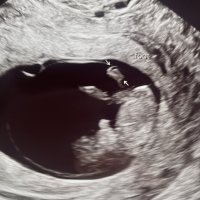

Alt fint i uke 9+4. Jordmor mente jeg var i uke 10 etter størrelsen, 31 mm. Det er IVF så har ganske god kontroll, så det vil si fosteret har vokst mer enn normalt. Veldig bra. Fikk høre hjertelyd, 164 slag i minuttet. Har

fikk bilde av at h*n vinket til oss

gjorde salto og snudde seg hit og dit, en aktiv liten krabat! Nå skal jeg prøve å senke skuldrene og nyte